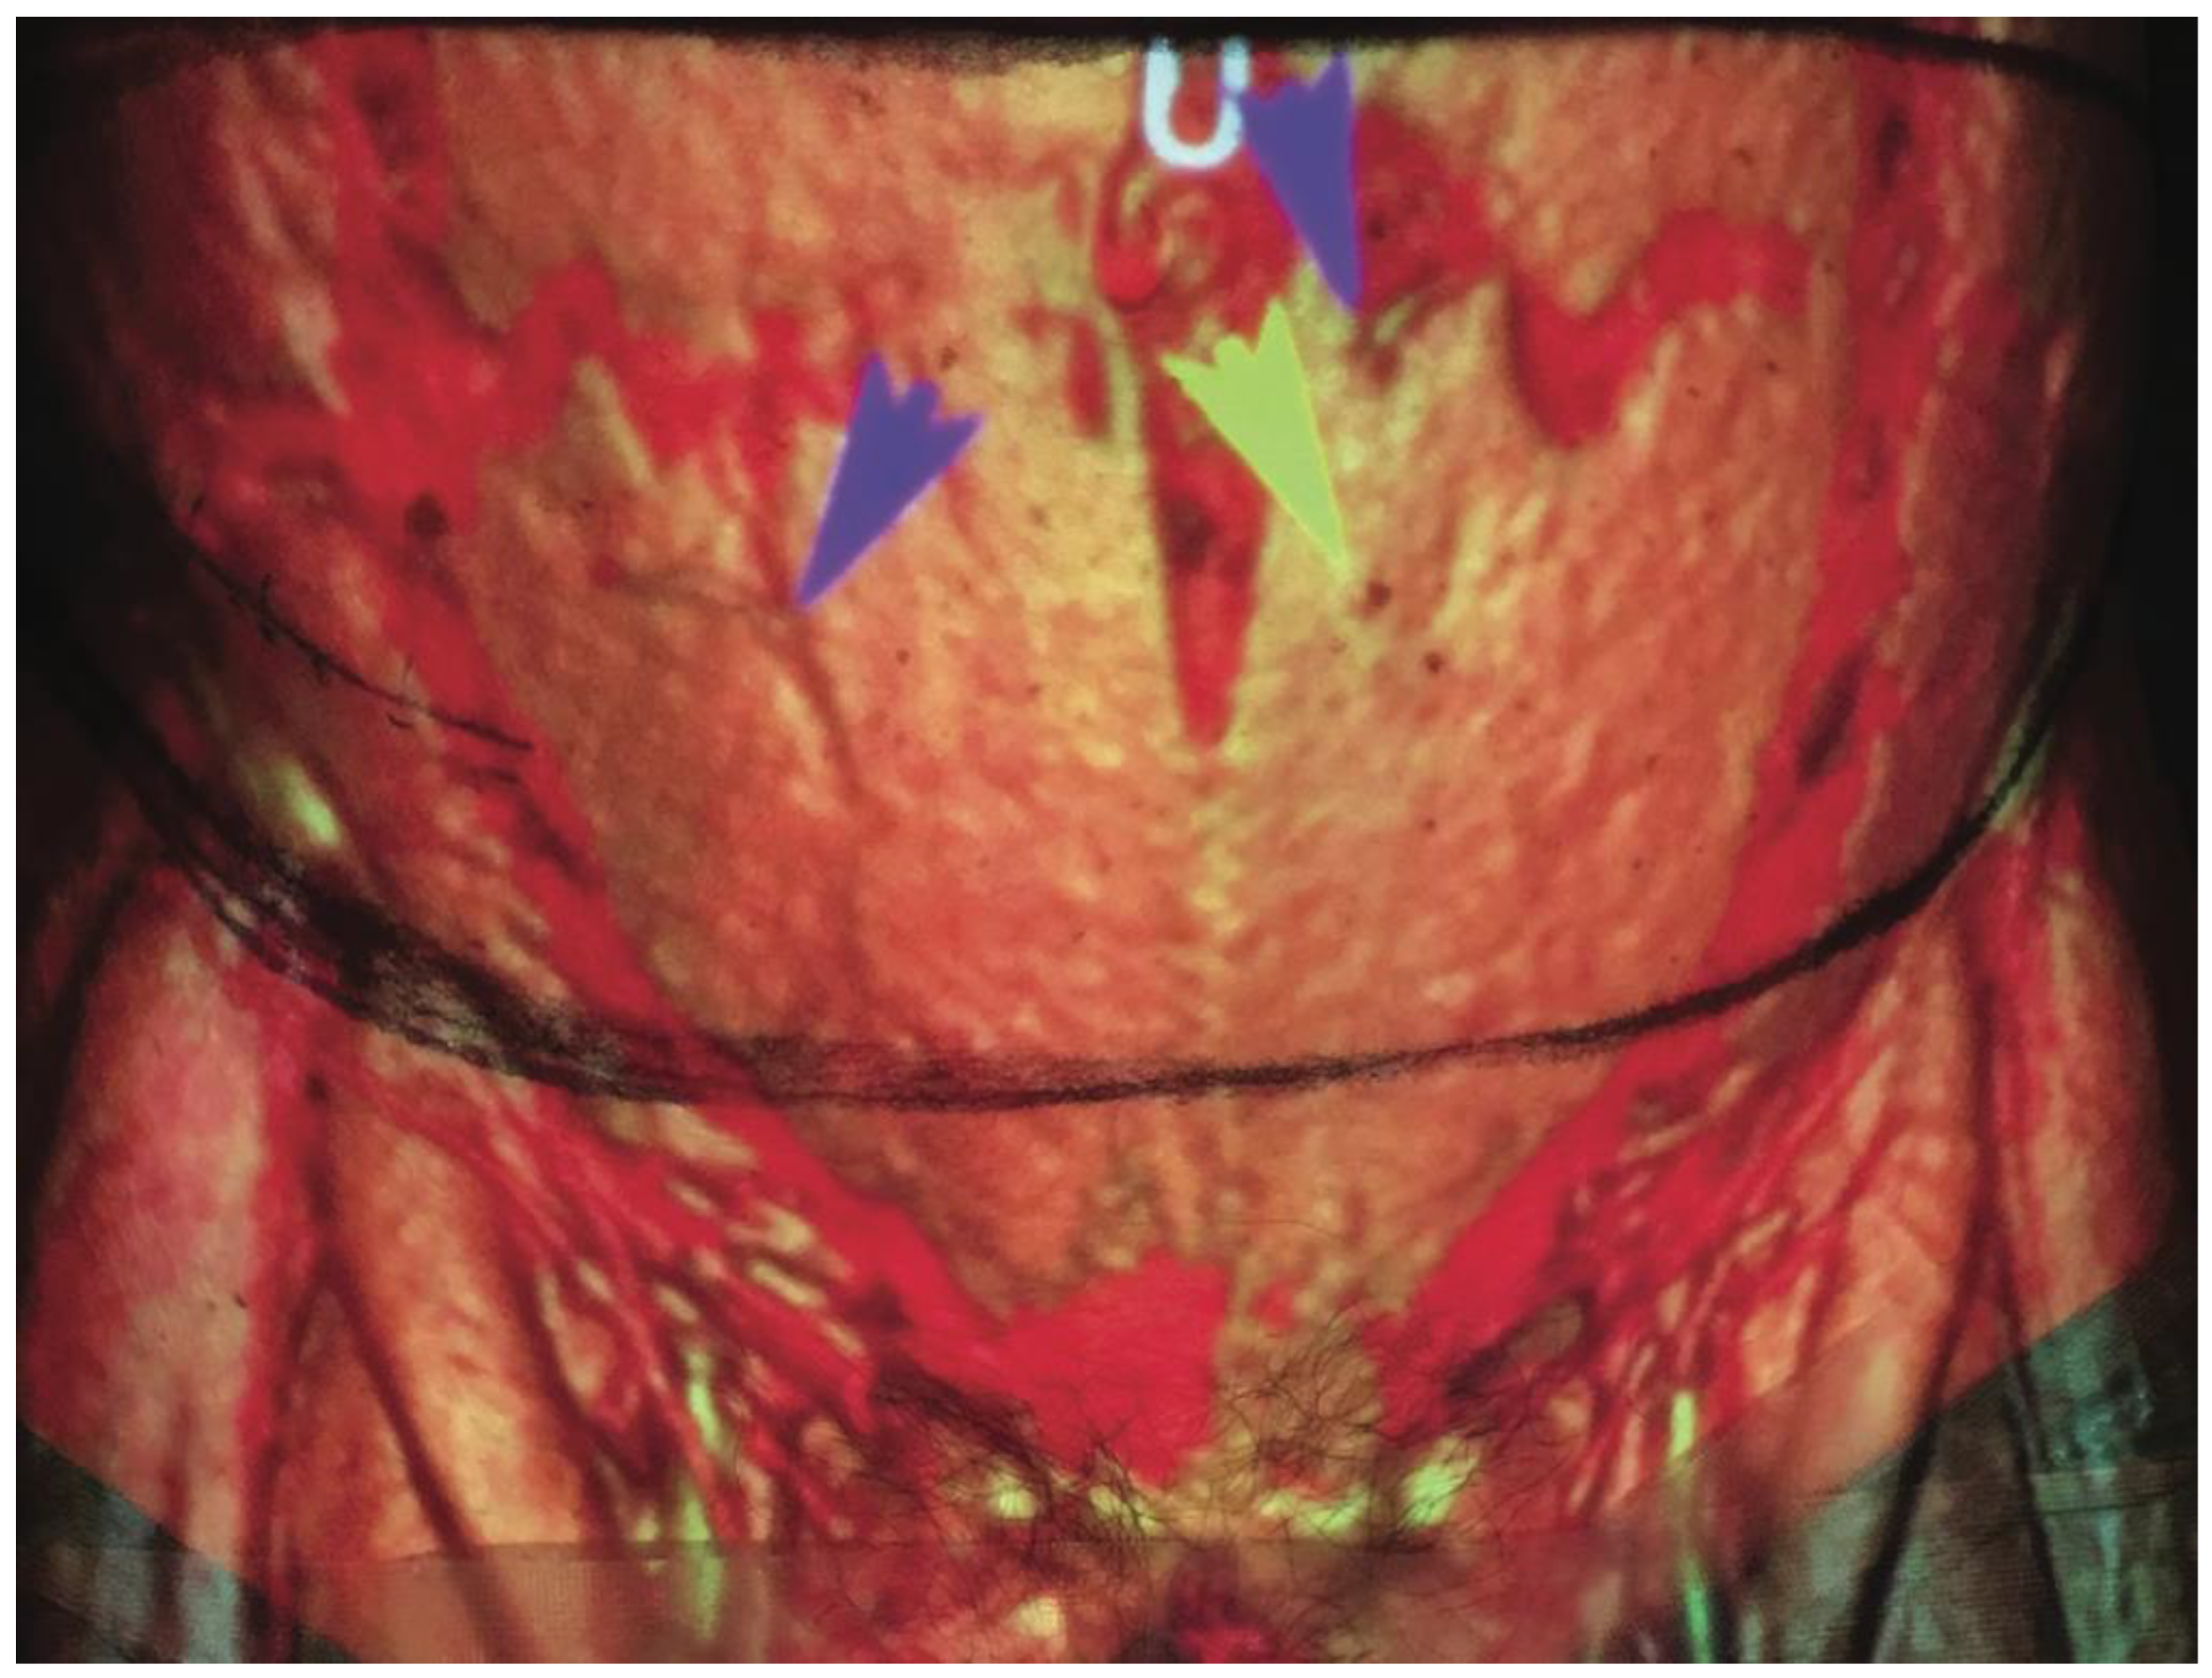

- Chae, M.P.; Ganhewa, D.; Hunter-Smith, D.J.; Rozen, W.M. Direct augmented reality computed tomographic angiography technique (ARC): An innovation in preoperative imaging. Eur. J. Plast. Surg. 2018, 41, 415–420. [Google Scholar] [CrossRef]

- Rahman, O.F.; Nahabedian, M.Y.; Sinkin, J.C. Augmented Reality and Wearable Technology in Image-guided Navigation and Preoperative Planning. Plast. Reconstr. Surg. Glob. Open 2016, 4, e1057. [Google Scholar] [CrossRef] [PubMed]

- Wesselius, T.S.; Meulstee, J.W.; Luijten, G.; Xi, T.; Maal, T.J.J.; Ulrich, D.J.O. Holographic Augmented Reality for DIEP Flap Harvest. Plast. Reconstr. Surg. 2021, 147, 25e–29e. [Google Scholar] [CrossRef]

- Pratt, P.; Ives, M.; Lawton, G.; Simmons, J.; Radev, N.; Spyropoulou, L.; Amiras, D. Through the HoloLens™ looking glass: Augmented reality for extremity reconstruction surgery using 3D vascular models with perforating vessels. Eur. Radiol. Exp. 2018, 2, 2. [Google Scholar] [CrossRef] [PubMed]

- Phan, R.; Chae, M.P.; Hunter-Smith, D.J.; Rozen, W.M. Advances in perforator imaging through holographic CTA and augmented reality: A systematic review. Australas. J. Plast. Surg. 2022, 5, 32–38. [Google Scholar] [CrossRef]